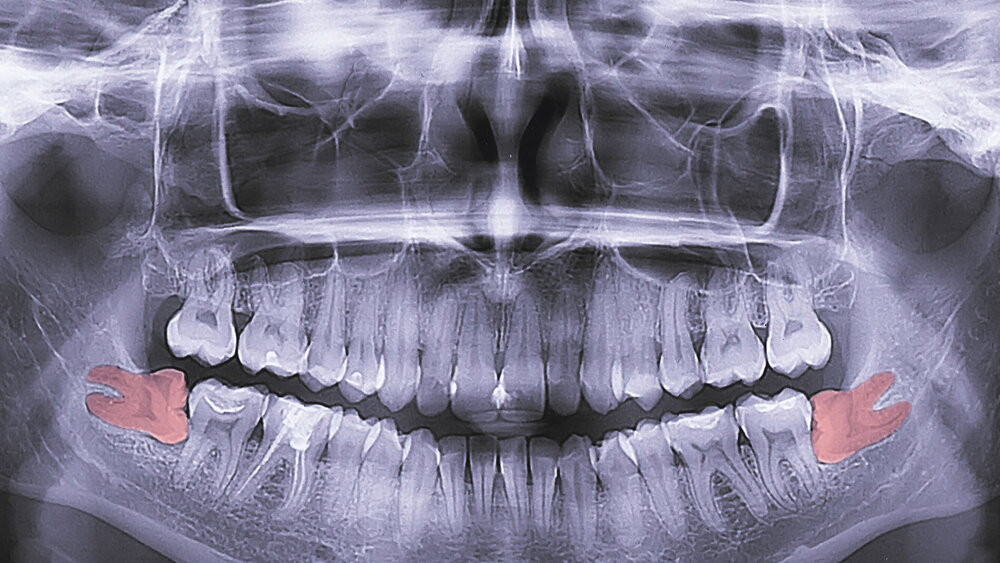

Eine Alveolitis sicca tritt vorwiegend bei der Extraktion von Weisheitszähnen oder Molaren im Unterkiefer auf. Die Prävalenz variiert stark in Abhängigkeit von der Lokalisation und Entfernungsmethode. Während sie bei normalen Extraktionen bei ein bis fünf Prozent liegt, kann sie bei chirurgischen Entfernungen von Achtern bis zu 30 Prozent betragen [Daly et al., 2022]. Klinisch kann sie sich durch starke Schmerzen und Halitosis zwei bis drei Tage postoperativ bemerkbar machen. Bei Inspektion der Extraktionsalveole kann das Blutkoagel teilweise oder vollständig fehlen.